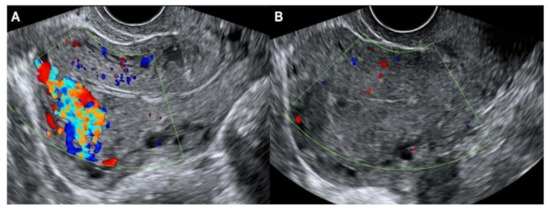

Ultrasound findings revealed complete resolution of AVM following danazol treatment in eight patients, all of whom developed AVM after abortion (either D&C or complete abortion). All eight of these patients experienced a return to normal menstruation within 2 months after completion of danazol treatment (Figure 1).

Figure 1. Ultrasound images (A) before and (B) after danazol therapy in a patient who developed AVM after dilatation and curettage for abortion.